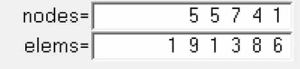

Meshing and supplemental establishment of the intervertebral disc and ligament: the three-dimensional entity models of T11–L3 and screw-rod system established in SolidWorks were imported into HyperMesh. Using the powerful mesh-making and dissection function of HyperMesh, a tetrahedral mesh was generated for the assembly, and 1-mm-thick cortical bone was constructed at the same time. The mesh sizes were 2 mm for T11–3 and 1 mm for the screw-rod system. Then, the structures of the endplate, annulus fibrosus, nucleus pulposus, anterior longitudinal ligament, posterior longitudinal ligament, intertransverse ligament, supraspinous ligament, interspinous ligament, ligamentum flavum, joint capsule ligament, and superior and inferior articular process cartilage were supplemented according to the anatomical site and shape to obtain a three-dimensional finite element model of T11–L3, which consisted of 191,386 elements and 55,741 nodes (the nodes and elements of T11–L3 Model Figure 10).